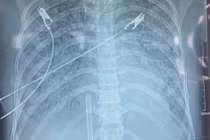

1-1762957980496.jpg

Bệnh nhân đang được điều trị tại Bệnh viện Đa khoa Quảng Trị.